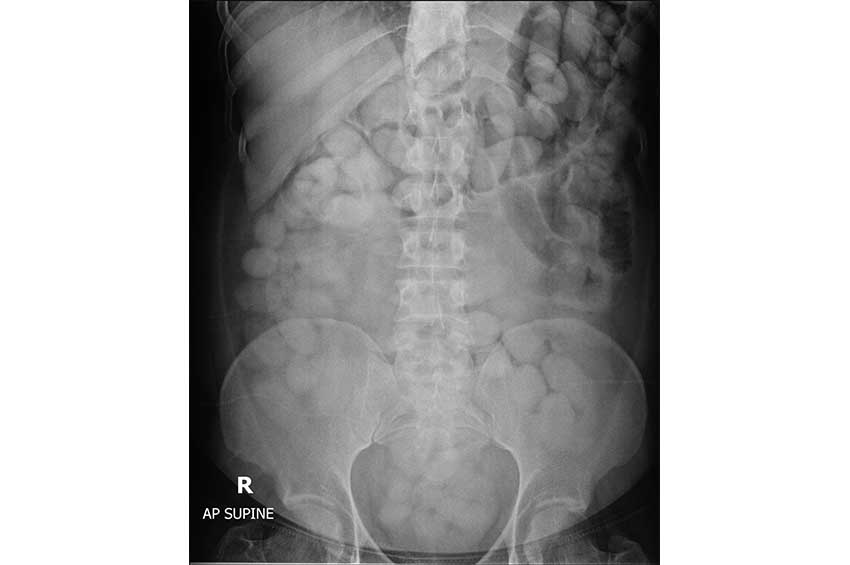

จากการตรวจสอบภาพเอกซเรย์ พบสิ่งแปลกปลอมจำนวนมาก รูปร่างทรงกลม และทรงรี ในช่องท้อง ผู้ต้องหายอมรับว่าตนได้กลืนยาเสพติด (ไม่ทราบชนิด) เจ้าหน้าที่ฯ จึงได้นำตัวผู้ต้องหาไปยังด่านศุลกากรท่าอากาศยานภูเก็ต เพื่อนำสิ่งแปลกปลอมดังกล่าวออกมาจากร่างกาย ผลการตรวจสอบสิ่งแปลกปลอมดังกล่าว พบเป็นยาเสพติดให้โทษประเภท 2 โคคาอีน จำนวนรวม 115 ก้อน น้ำหนักรวมสิ่งห่อหุ้ม 1.49 กิโลกรัม มูลค่า 4.47 ล้านบาท เป็นความผิดตามมาตรา 242 มาตรา 252 ประกอบมาตรา 166 และมาตรา 167 แห่งพระราชบัญญัติศุลกากร พ.ศ. 2560 จึงนำผู้ต้องหาพร้อมของกลางส่งพนักงานสอบสวน สถานีตำรวจภูธรสาคู เพื่อดำเนินคดีตามกฎหมาย